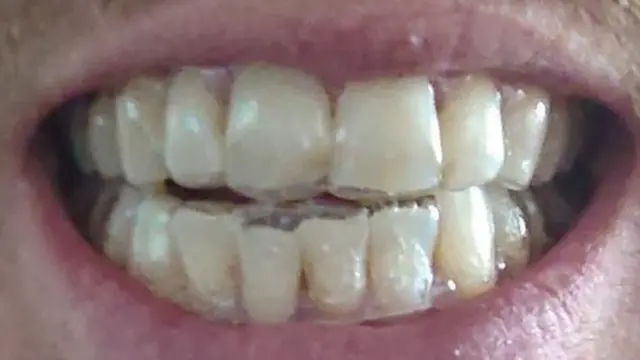

La presión por mostrar sonrisas perfectas en redes sociales como Instagram está generando graves problemas en los dientes de gente que ha optado por el uso de aparatos transparentes o "alineadores" comprados en internet.

Esa es la afirmación de un grupo de dentistas y ortodoncistas que le contaron a la BBC que los clientes de la llamada odontología a distancia no son conscientes del daño que pueden causar los alineadores si no son colocados en persona por un dentista.

No fue el caso de Jamie, un padre de Glasgow en Escocia, quien recurrió a SDC después de recibir un presupuesto de entre US$5.000 y US$7.500 para enderezar sus dientes.

La empresa estadounidense de ortodoncia a distancia ofrecía alineadores transparentes por unos US$2.000 sin necesidad de acudir en persona a un dentista.

Antes de empezar el tratamiento le enviaron un kit de impresión para que se hiciera sus propios moldes dentales. La otra opción, un escáner 3D de su boca realizado en una de las sedes SDC, no estaba disponible debido al confinamiento por la pandemia.

En pocas semanas recibió un tratamiento de alineadores de seis meses, con el nombre del dentista que lo iba a supervisar escrito en la caja.

En la odontología tradicional, los aparatos metálicos y los alineadores transparentes los colocan los propios odontólogos y ortodoncistas, o un auxiliar ortodoncista cualificado, luego de una consulta en persona.

En su sitio en internet, SDC dice que los usuarios "tendrán revisiones virtuales periódicas", con un dentista registrado en Reino Unido, "de principio a fin", pero Jamie dice que ni una sola vez le pusieron en contacto con el dentista que lo supervisaba ni le dijeron que acudiera a un dentista para tratar sus problemas.

Al final, el servicio de atención al cliente le puso en contacto con un "experto en odontología" a través del chat de la página, que le dijo que los problemas eran normales y que eventualmente desaparecerían. No está claro qué tipo de cualificaciones son necesarios para ocupar este puesto.